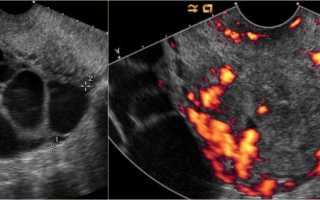

На сонограмме, выполненной молодой беременной женщине, выявлены множественные кисты в обоих яичниках. Справа обнаружено инвазивное образование в матке, сопоставимое с гестационной трофобластической болезнью. Заключение о заболевании основано на клинико-анамнестических данных (факт беременности) и сонограмме, на которой отмечены признаки инвазивной формы гестационной трофобластической болезни.

image